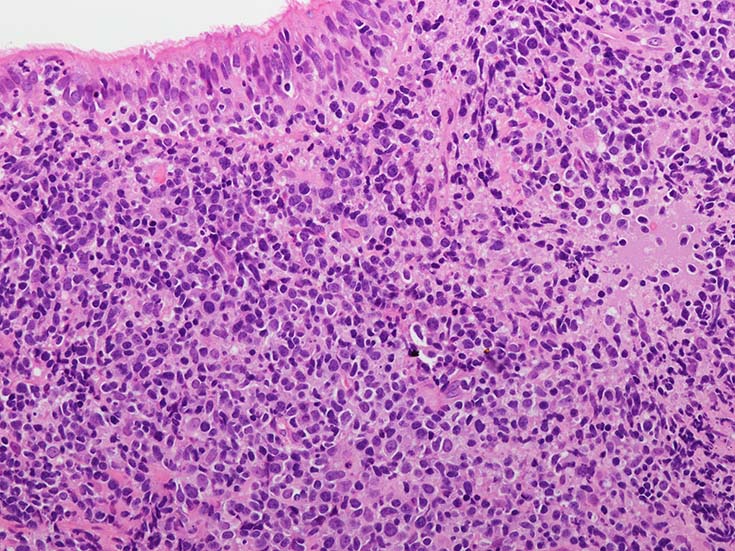

EBUS-GS(ガイドシース併用気管支腔内超音波断層法)による肺生検組織病理所見.

血管周囲性に大型類円形核や不整形核をもつ腫瘍細胞がシート状密に浸潤増殖している. Mitosisが多く認められる.細血管閉塞や破壊の所見がある.

間質にもシート状の腫瘍細胞浸潤がある. 大小 pleomorphicな傾向.(A, B). necrosisが認められる(C). 細気管支上皮直下まで密な浸潤あり, 小型リンパ球が混在している.(D)

血管中心性浸潤. 障害された血管内に血栓が形成されている.CD20陽性細胞がシート状密に浸潤, CD3陽性T細胞が多く混在している. EBER-ISH陽性 EBV感染細胞が多数認められ, >50 hpf, 定義より Grade3となる. 陽性細胞のサイズは大小さまざまであることに注意.